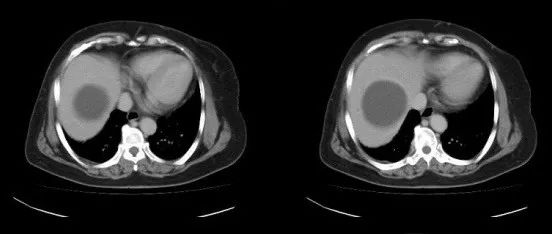

医学影像  yxyx-app  医学影像APP,打造伴随医生快速成长的影像学习社区。与影像园(Xctmr.com)一起提供最全面的影像案例库、基础(解剖、病理、影像诊断)知识、影像技术及考题等,为医生提供最佳的医学影像参考。【所属科室】消化科【基本资料】患者,女,69岁【主诉】超声发现肝囊肿。【影像图片】【讨论问题】如何诊断?【医学影像APP用户讨论】评论:胰腺体部前缘局限性外突结节影,平扫呈等密度,增强扫描呈多血供强化征象,动脉期、静脉期均高于正常胰腺的密度。考虑为胰腺内分泌肿瘤胰岛素瘤可能大。...